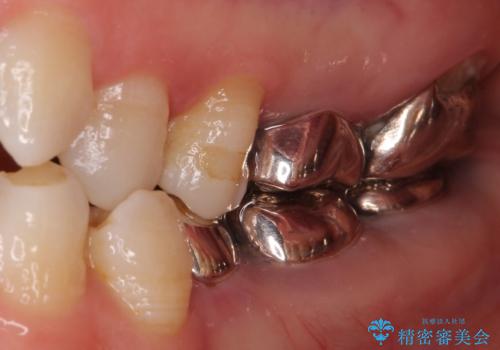

- 全顎的な歯列不正と、銀歯だらけの奥歯を気にして来院された患者様です。

奥歯の銀歯は、セラミッククラウンを装着するには歯の高さが不十分であり、そのままでは矯正治療を行うことが困難であるため、歯冠長延長術を行うこととしました。